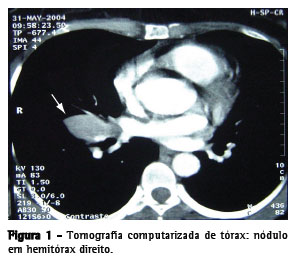

Paciente do sexo feminino, 40 anos, era oligossintomática com dor torácica incaracterística há 20 anos, referindo que a mesma aparecia cerca de uma vez por mês, com aperto no hemitórax direito, com algumas horas de duração, e que algumas vezes era acompanhada de dispnéia. O raio X de tórax revelou uma imagem hipotransparente à direita. A tomografia computadorizada mostrou imagem com cerca de 3 cm de diâmetro, com íntima relação com a artéria pulmonar, não afastando origem vascular do nódulo (Figura 1).